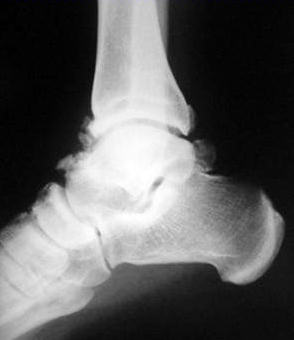

Yan grafilerde bazen tam olarak değerlendirilemeyen bu lezyonlar antero-medial oblik grafilerle daha iyi demonstre edilebilir. Bazılarına göre, ayak bileği artrozunun erken evresi kabul edilen bu hastalıkta, osteofitlerin artroskopik olarak eksizyonu ile başarılı sonuçlar elde edilebilir. Tol ve Van Dijk, artroz bulgusu olmayan hastalarda osteofit eksizyonu ile % 77 başarılı sonuç elde etmişler, bu oran artrozlu hastalarda %53’e düşmüştür (J Bone Joint Surg Br. 2001 83:9-13). Lezyonların 2/3’ü yılda kısmen tekrar oluşmasına rağmen, klinik sonuçlarda ciddi bir bozulma söz konusu değildir.